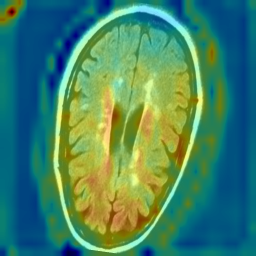

c) Brain MRI Dataset (ND-5): We evaluated our approach on the Brain MRI ND-5, compared with the baseline we used 500 , the proposed method improves all metrics: ROC-AUC rises from 0.6041 to 0.7269 and PR-AUC from 0.7539 to 0.8211. At the Youden-optimal threshold (baseline , proposed ), accuracy increases from 0.6216 to 0.7445. The confusion matrix shows improvement from to with a drop of 344 false negative. However, Baseline + Adapter warm-up attains ACC 0.7327, precision 0.8083, recall 0.8132, and F1 0.8107, with . Further, we depicted heatmaps in Fig. 5 to compare the anomaly localization behavior before and after IL. The baseline PatchCore model generates widespread, low-intensity activations, suggesting limited discriminative capacity between healthy and abnormal tissue. After IL, the attention becomes significantly more focused on the lesion area, and higher saliency contrast, indicating more discriminative feature representations.